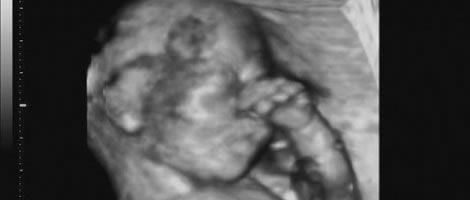

3 meses de gravidez

Neste mês o embrião passa a chamar-se de feto. No terceiro mês de gravidez todos os órgãos do bebé já estão desenvolvidos, apesar de ainda não estarem completamente formados. Precisam amadurecer e evoluir correctamente. Os genitais começam a definir-se mas ainda é cedo para determinar se o feto é um menino ou menina.

Ao longo destas três semanas o feto cresce mais de 7cm e pode chegar a pesar 20 gramas. A futura mãe engodará neste período cerca de 10% do total que engordará durante a gravidez.